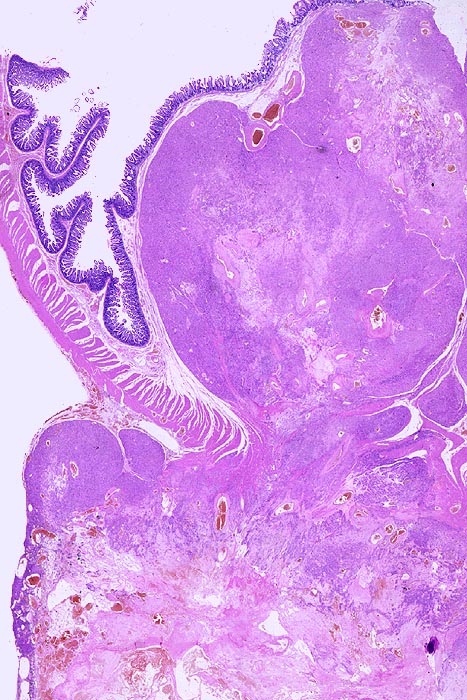

• Scharf begrenzter kugeliger Tumor in der Submukosa des Magenantrums

• Über dem Tumor entzündungsfreie Antrumschleimhaut mit partiell reepithelialisiertem oberflächlichem Ulkus (Quellungsfibrinoid).

• Der Tumor besteht aus längs und quer getroffenen Faszikeln spindelförmiger Tumorzellen, welche an glatte Muskelzellen oder Schwannzellen erinnern.

• Herdförmig pseudozystische Auflockerung des Tumorgewebes.

• Risikostratifikation nach Miettinen und Lasota (2006): Very low risk (sehr niedriges Risiko für Metastasen oder tumorbedingte Mortalität): Lokalisation im Magen, Grösse 22mm, fehlende Mitosen.